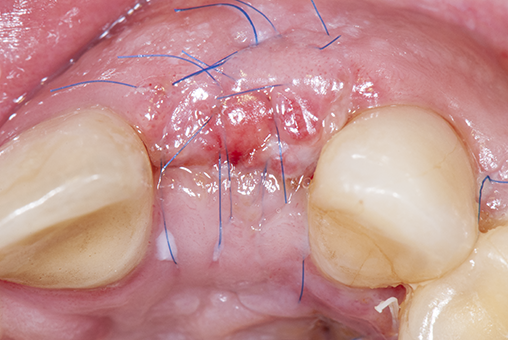

Therefore, achieving primary wound healing after surgery is considered the greatest challenge of periodontal and implant procedures as well as a decisive measure of success, in most cases aiming to avoid wound dehiscence, tissue defects, fibrotic-tissue formation, and scarring (Figure 1).